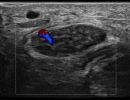

- Focal Lesions (tumors, neuromas)